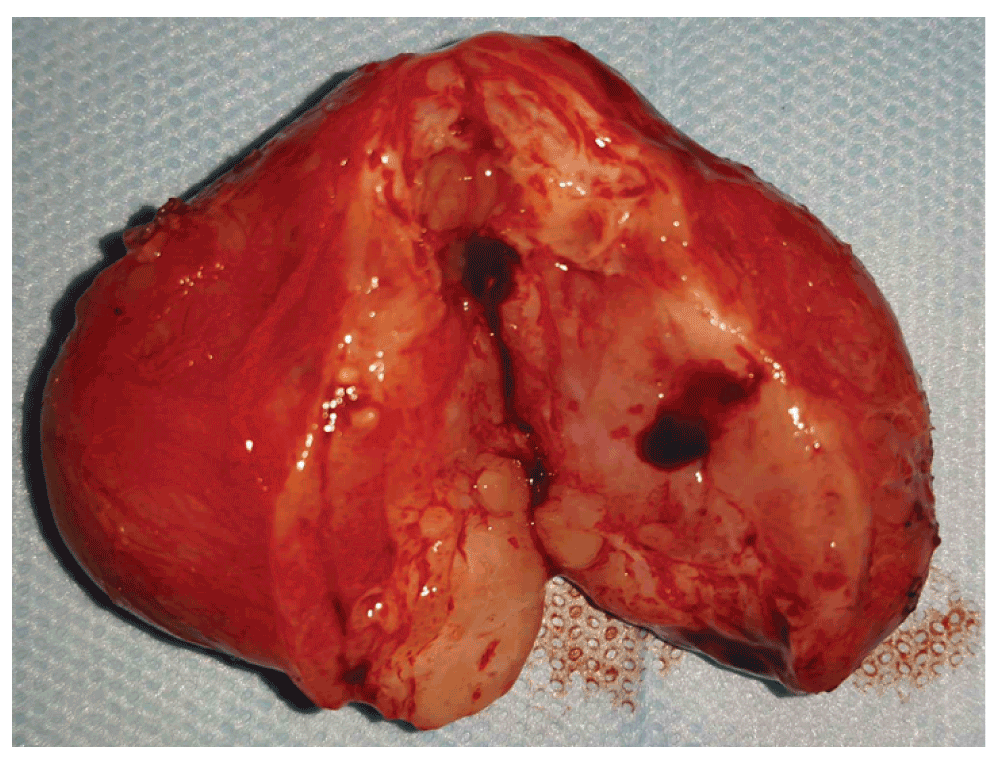

We decided to remove the cervical mass, since it was causing the tracheal obstruction. The surgery lasted 35 minutes and was uneventful. The mass was well circumscribed and could be easily dissected, weighed 20 grams and measured 33×61×45 mm Figure 4. The infant returned from surgery in good condition. A bronchoscopy was performed the next day after surgery, during tracheal extubation, which revealed no malacia or any other disorders on the trachea or the upper respiratory tract. The patient has been eupneic since then. The histological analysis revealed a mature teratoma with no atypias or signs of malignancy.